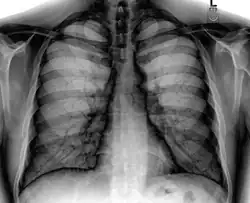

Landmarks

In the average person, the diaphragm should be intersected by the 5th to 7th anterior ribs at the mid-clavicular line, and 9 to 10 posterior ribs should be viewable on a normal PA inspiratory film. An increase in the number of viewable ribs implies hyperinflation, as can occur, for example, with obstructive lung disease or foreign body aspiration. A decrease implies hypoventilation, as can occur with restrictive lung disease, pleural effusions or atelectasis. Underexpansion can also cause interstitial markings due to parenchymal crowding, which can mimic the appearance of interstitial lung disease. Enlargement of the right descending pulmonary artery can indirectly reflect changes of pulmonary hypertension, with a size greater than 16 mm abnormal in men and 15 mm in women.[6]

Appropriate penetration of the film can be assessed by faint visualization of the thoracic spines and lung markings behind the heart. The right diaphragm is usually higher than the left, with the liver being situated beneath it in the abdomen. The minor fissure can sometimes be seen on the right as a thin horizontal line at the level of the fifth or sixth rib. Splaying of the carina can also suggest a tumor or process in the middle mediastinum or enlargement of the left atrium, with a normal angle of approximately 60 degrees. The right paratracheal stripe is also important to assess, as it can reflect a process in the posterior mediastinum, in particular the spine or paraspinal soft tissues; normally it should measure 3 mm or less. The left paratracheal stripe is more variable and only seen in 25% of normal patients on posteroanterior views.[7]